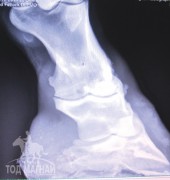

2014 оны 12-р сарын 18 нд Ирланд улсын Килдари хот орчимд байрлах адууны зүчээнд адууны хөл доголсон дуудлагаар очиход 9 настай, үржлийн чиглэлээр ашигладаг сартай хээр гүүний баруун талын хойд хөл доголоод 2 хонож байгаа ба өглөө оройд бага зэрэг унаж биеийг нь халаадаг. Үзлэгээр өнгөц ба гүн нугалагч шөрмөс, шандсыгбарилахад тэр орчмоор халуунгүй эмзэглэл, хавангүй байсан. Адууг чигээр нь болон баруун, зүүн талаар нь тойрог хэлбэртэйгээр шогшуулахад үл мэдэгдэм догол илэрч байв. Нугалах тестийг урд хөлний сагагны үенээс эхлэн тавихад баруун хойд хөлний сагагны үенд доголын зэрэг нэмэгдэж байсан. Дараа нь оношийг тодруулах зорилгоор рентген зураг авахад баруун талын хойд хөлний бэрэвхий ба титэм үенд архаг үрэвсэл явагдаж бэрэвхий ясны арын холбогч шандас татагдсанаас яс нь бага зэрэг сөлтөрч хугарсан байв.